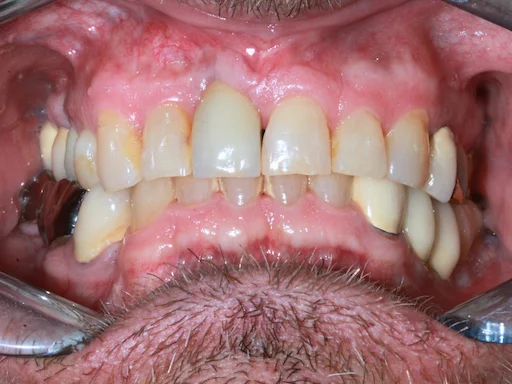

Patientenfall: Zähne 44,45,46,48 - Ausgangssituation

Schritt 2

Bei diesem Eingriff sollten die Zähne 44, 45, 46 und 48 extrahiert werden, gefolgt von einer direkten Implantation an den Positionen 44, 46 und 47.